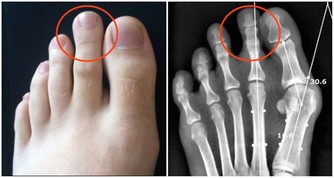

3、運動系統

運動系統腫瘤主要指骨癌,這類患者常因病情而作過截肢手術,術後的鍛煉以恢復運動功能為目的。鍛煉方式或以健側肢體彌補患側功能,如練習用單手料理生活;或以假肢或以拐杖代替患側肢體,如學會拄拐或用輪椅、學會正確應用假肢。此類運動量一般較大,患者常常由於術後疼痛或對殘疾的不接受而導致對鍛煉包括必需的鍛煉的不配和,此時需要耐心地給以精神上的安慰和生活上的照顧,練習時給予熱情幫助和指導,病人本人則要冷靜、有耐心,當經過鍛煉而學會活動和走路時,喜悅的心情能夠補償鍛煉時所付出的艱辛。